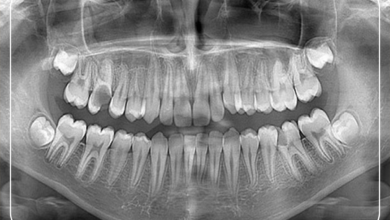

Hastanın detaylı ağız içi muayenesinin yapılmasının ardından ağız bölgesine ait röntgenlerin incelenmesi ve teşhis konulması işlemidir. Böylelikle hastanın öncelikli şikayetinin…